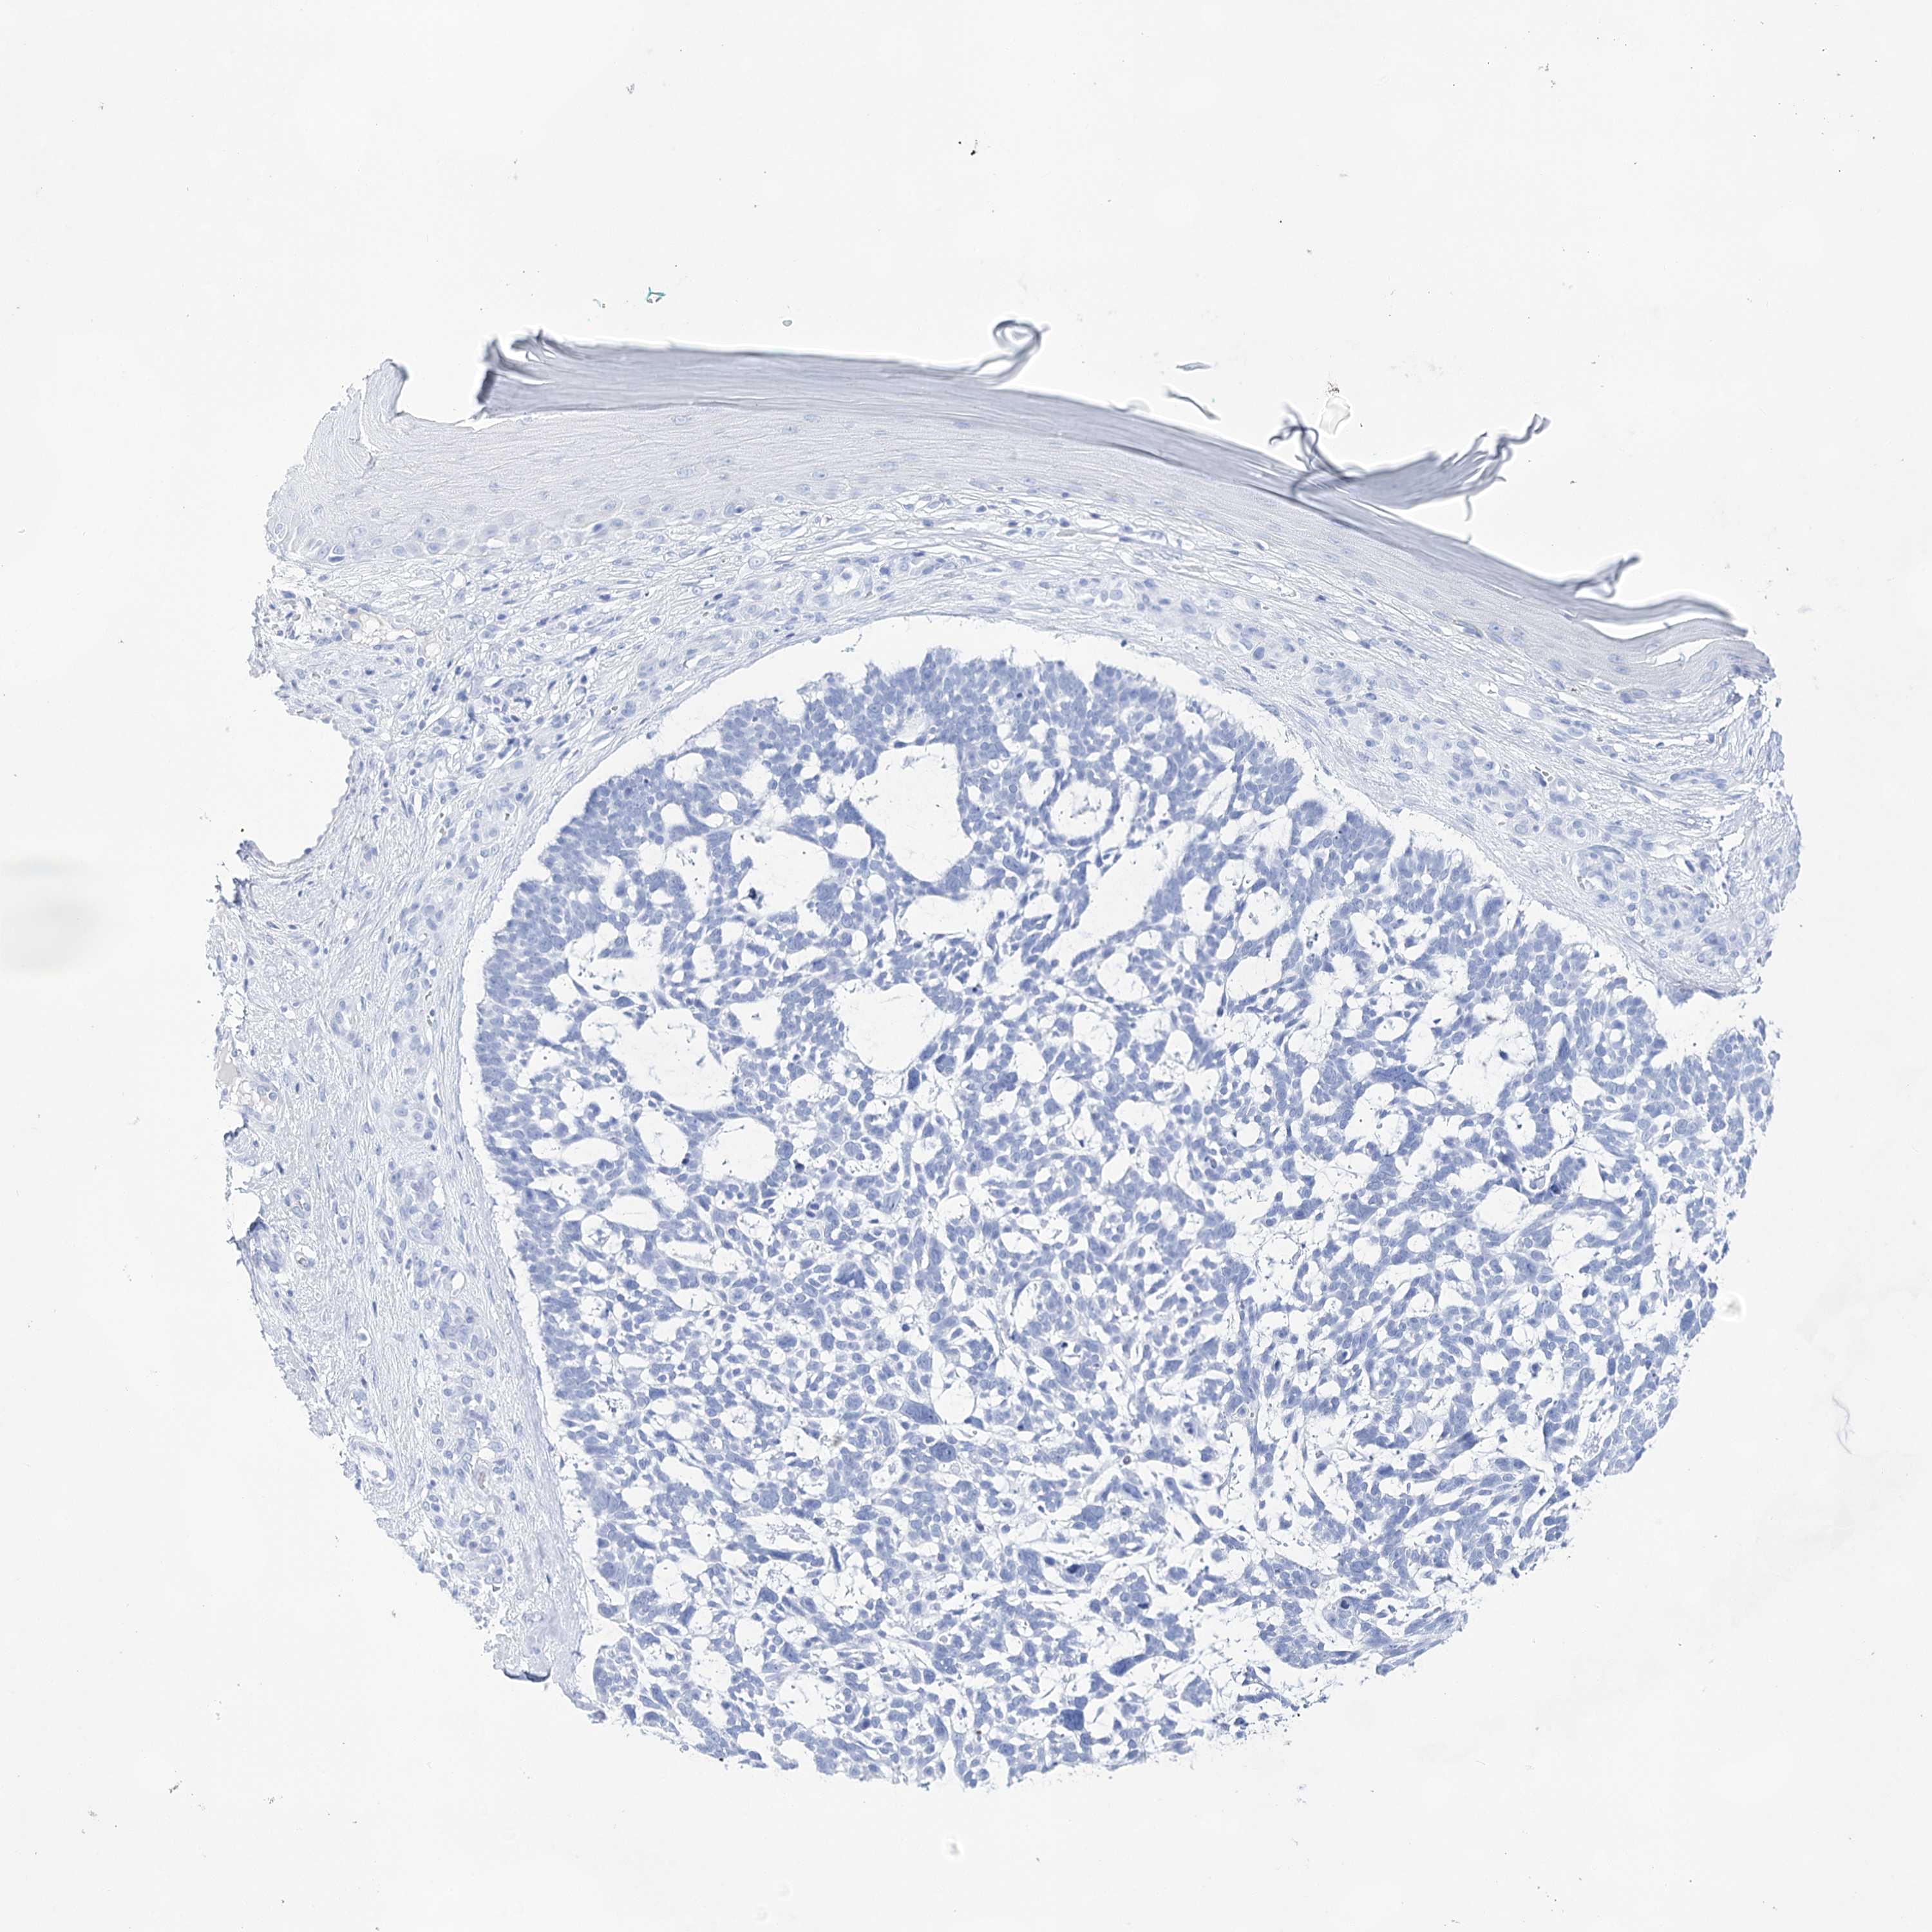

CANCER SKIN CANCER Show tissue menu

Basal cell and squamous cell cancer

SKIN CANCER - Protein expressioni

A mouse-over function shows sample information and annotation data. Click on an image to view it in a full screen mode. Samples can be filtered based on level of antibody staining by selecting one or several of the following categories: high, medium, low and not detected. The assay and annotation is described here.

Each image is clickable and will lead to virtual microscopy that enables deeper exploration of all samples and also displays staining intensity scores, fraction scores and subcellular localization as well as patient and tissue information for each sample.

Antibody HPA029855

Antibody HPA029856

Antibody CAB026343

Basal cell carcinoma

Squamous cell carcinoma, NOS

Squamous cell carcinoma, metastatic, NOS